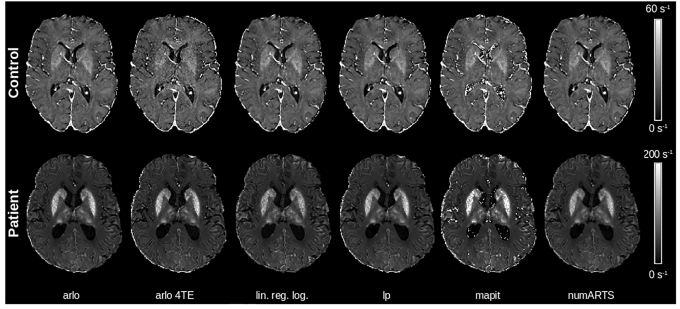

研究团队采用前瞻性设计,纳入3名ACP患者和3名健康对照,使用3T MRI系统采集三维多回波梯度回波序列(9个回波,TE=2.6-30.6ms)。关键技术包括:6种R2*算法(如基于自回归线性运算的快速单指数拟合算法ARLO、对数空间线性模型等);6种QSM算法(如快速非线性磁化率反演FANSI、改进的稀疏线性方程iLSQR等);3种参考区域策略(全脑、脑脊液CSF、无参考)。通过FSL-FIRST自动分割深部灰质核团,采用排列转换方差分析比较算法差异。

研究发现:对数空间线性模型在极端铁过载区域(如壳核)显著低估R2*值(p<0.001),而ARLO和非线性算法表现稳健。值得注意的是,在齿状核等铁浓度极高区域,即使最短TE=2.6ms仍出现信号丢失,提示需要超短TE序列。